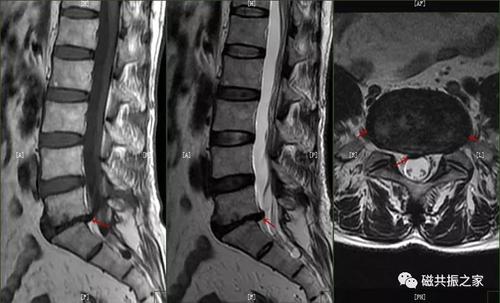

相应的,当纤维环全层都遭到破坏,髓核或含有部分破碎的纤维环及软骨板

椎间盘高信号区都代表纤维环撕裂吗?